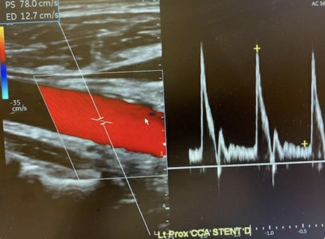

05/06/2020

Tej M. Singh, MD, MBA; Amy Lee, MD; Matthew Vo, RVT; Saba F. Ali, MD; Bo Myung Cheon, MD; Maybelyn Josephson, RN; Valy Boulom, MD

A unique case of a symptomatic carotid endarterectomy in a COVID-19 patient.